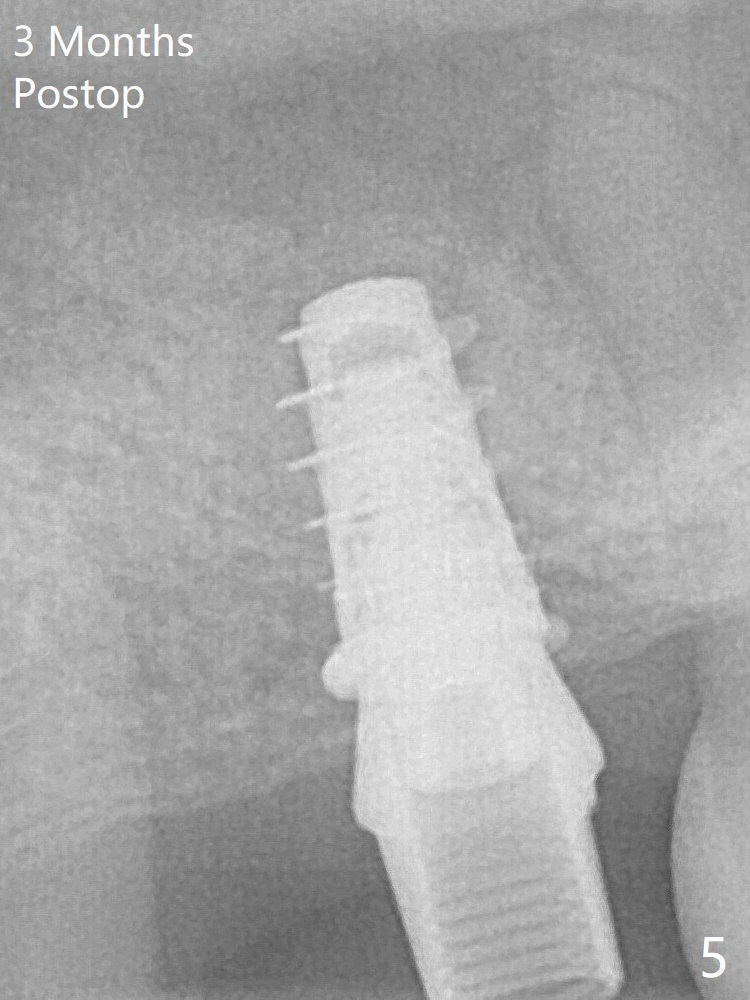

Although the bone graft surrounds the implant 3 months postop, the implant is tender when a 4.5x4(2) mm cemented abutment is being placed (Fig.5). Later a healing screw is placed (Fig.6,7). The implant is uncovered with a 6x2 mm healing abutment 6.5 months postop (Fig.8). A 5.5x4(2) mm pair abutment is placed and torqued at ~20 Ncm with mild tenderness 7 months postop (Fig.9 BW). A provisional is fabricated for progressive loading because of mild crestal bone loss (*).